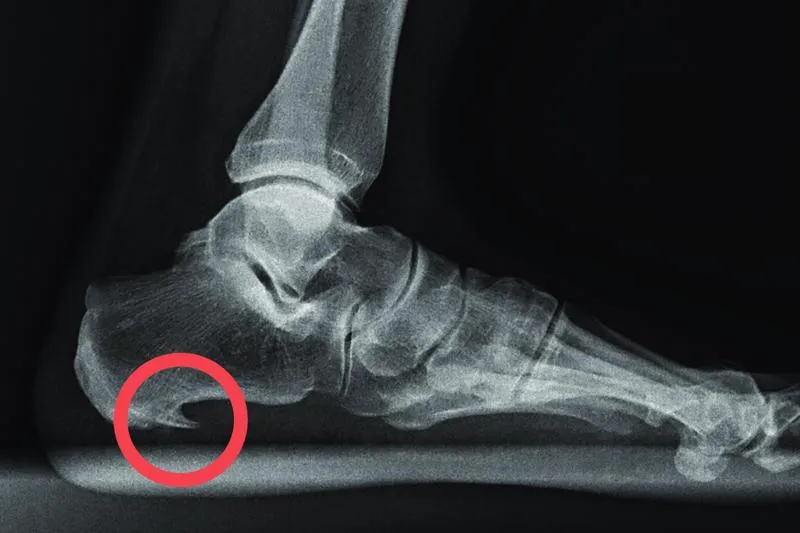

Ostroga piętowa staje się zmorą wielu biegaczy, a ja niestety również musiałem się z nią zmierzyć. To schorzenie objawia się ostrym bólem pięty, który odczuwam głównie rano, kiedy stawiam pierwsze kroki po dłuższym odpoczynku. Jeżeli cię to ciekawi, sprawdź, czy ból gardła przeszkadza w bieganiu. W takich momentach czuję, jakbym chodził po kawałkach szkła, co stanowi naprawdę niezbyt przyjemne doświadczenie. Takie dolegliwości potrafią skutecznie zrujnować zarówno moje treningi, jak i radość z biegania. Dlatego niezwykle istotne staje się zrozumienie tego problemu oraz podjęcie odpowiednich działań.

- Ostroga piętowa to powszechna dolegliwość wśród biegaczy, powodująca ostry ból pięty.